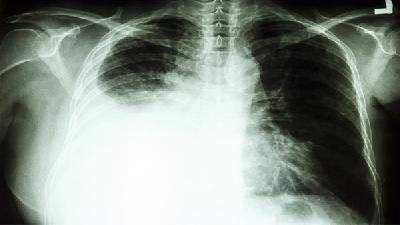

阻塞性肺气肿可通过戒烟、支气管扩张剂、糖皮质激素、氧疗等方式治疗。阻塞性肺气肿通常由长期吸烟、空气污染、遗传因素、慢性支气管炎等原因引起。